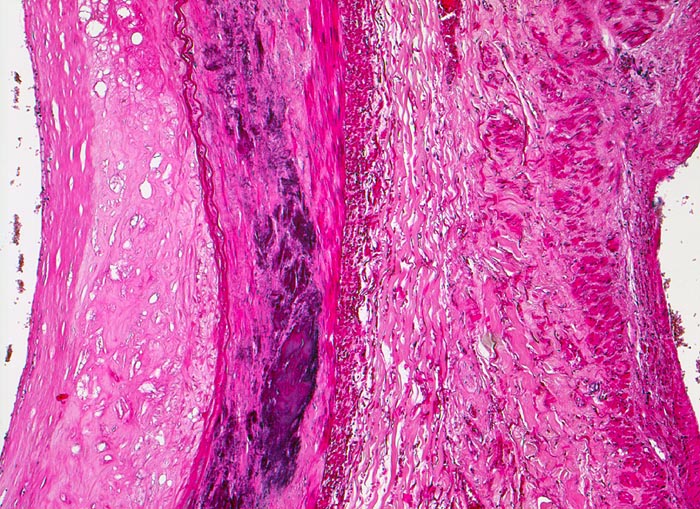

PathoPic – image database / PathoPic ID 4557 - Atherosklerose

Atherosklerose

Arteria poplitea

Links im Bild die Arteria poplitea mit fibrosierter und verdickter Intima mit herausgelösten Cholesterinkristallen. Lamina elastica interna an der Grenze zur atrophen und verkalkten Media. Rechts im Bild unauffällige Venenwand.

Ältere Venenthrombosen sind aufgrund der Organisation wandhaftend.